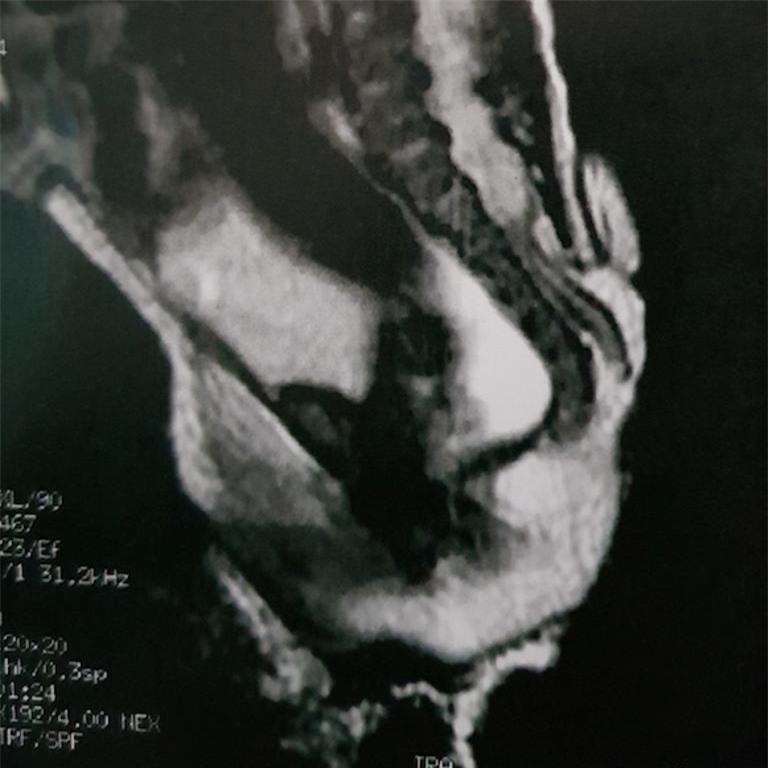

Chiếc đuôi kỳ lạ của bé gái người Brazil.

Các bác sĩ phải phẫu thuật cắt bỏ phần “đuôi” dài 6cm của đứa trẻ được bao phủ bởi da lưng. Hình ảnh về trường hợp đáng chú ý đã được công bố trên Tạp chí Journal of Pediatric Surgery Case Reports.

Các bác sĩ từ Grendaac - một bệnh viện nhi ở Sao Paulo - cho biết, chiếc đuôi được tạo ra từ vùng thắt lưng cùng, khu vực nối cột sống với xương chậu.

Chiếc đuôi hình thành từ vùng thắt lưng cùng nối cột sống với xương chậu